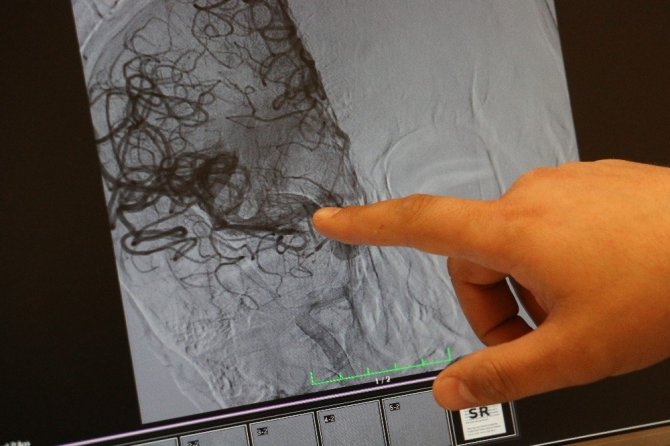

İnme hastalığının yaşla birlikte sıklığı artan bir hastalık olduğuna dikkat çeken Doç. Dr. Aytaç, "Dünyada her 6 saniyede bir kişi inme geçiriyor ve 60 dakikada bir kişi de inmeye bağlı ölüm görüyoruz. 70 yaş civarında binde 20 sıklıkla görülüyor. 45 yaş civarına kadar bu hastalığı görebiliyoruz. Yaş arttıkça sıklığı artıyor ama 20'li yaşlarda da görebiliyoruz. İnme hastalarına erken müdahale ile hastaların felç kalmasına veya ölmelerini engellemeye çalışıyoruz. Merkezimiz bünyesinde erken dönemde damar tıkanıklığıyla gelen hastalara hızlıca müdahale ediyoruz, hastayı hemen anjiyo ünitesine alıyoruz. Tıkalı beyin damarını tespit ettikten sonra o damarın açılmasını sağlıyoruz. Böylelikle hastaların felç kalmasını engelliyoruz ki inme, dünyada sakat bırakma ve engellilik konusunda birinci sırada yer alan en önemli hastalıklardan bir tanesidir ve dünyadaki ikinci en sık ölüm nedeni inmeye bağlı ölümler oluşturuyor. Merkezimiz de yaklaşık 2017 yılından beri bu bölgedeki hastalara hizmet vermekte. Bugüne kadar yaklaşık 500 anjiyo işlemi gerçekleştirdik ve yüzlerce hastanın hayatına dokunabilme imkanımız oldu. Sadece erken dönemde inme hastaları değil aynı zamanda inmeye neden olan şah damar tıkanıklığı olan hastalara da stent takarak hastaların uzun dönemli inme geçirmelerini veya daha ağır bir inme geçirmesini engelliyoruz" dedi.

İnme belirtileriyle gelen ve sağlığına kavuşan iki hasta hakkında da bilgi veren Doç. Dr. Aytaç, "İnme hastalarında bizim için en önemli olay, zaman. Zaman bizim için çok önemli ki hatta "zaman eşittir beyin" diyoruz. Biz bu hastalara ne kadar erken müdahale edersek o kadar hastaların sağ kalmasını sağlıyoruz. Kabaca hastanın ağzında kayma, konuşmasında bozulma, kol ve bacağında kuvvetsizlik, uyuşma ve denge kaybı gibi şikayetler inmenin erken bulguları olabilir. O yüzden evden zaman geçirmeden, suya ve duşa sokma ve sarımsak yedirme gibi işlemler ki toplumumuzda en fazla bu tür işlemler yaptırılıyor, bu tarz yanlış işlemler yapılmadan bir an önce hastaların 112 vasıtasıyla ilgili merkezlere gelmesini önemle tavsiye ediyorum. Murat bey, sol tarafında kuvvetsizlik şikayetiyle geçen ay gelmişti. Hastamızın sol kol ve bacağı tutmuyordu, konuşmasında bozulma olmuş ve bilinci tama yakın kaybolmuştu. Hastayı hemen hızlıca tomografi çektikten sonra hastanın ana damarında tıkanıklık olduğunu tespit ettik, hastayı anjiyo ünitesine aldık ve tıkalı damarı özel geri alınabilir stent sistemiyle pıhtıyı çıkardık. Hastanın tutmayan sol kol ve bacağının tekrar hareketlendiğini gördük. Bu vasıtayla Murat bey tekrar eski sosyal hayatına, işine geri dönebildi. Diğer hastamız da bize geçen aylarda gelmiş bir hasta o da aynı şikayetle geldi ve tamamen hareket edemez durumdaydı. İki hastamız da bize erken dönemde, ilk bir saat içerisinde geldi. Her iki hastamızı bir saat içerisinde anjiyoya aldık ve tıkalı olan beyin damarlarını açtıktan sonra çok şükür her iki hastamız da sosyal hayatlarına devam edebildi" diye konuştu.